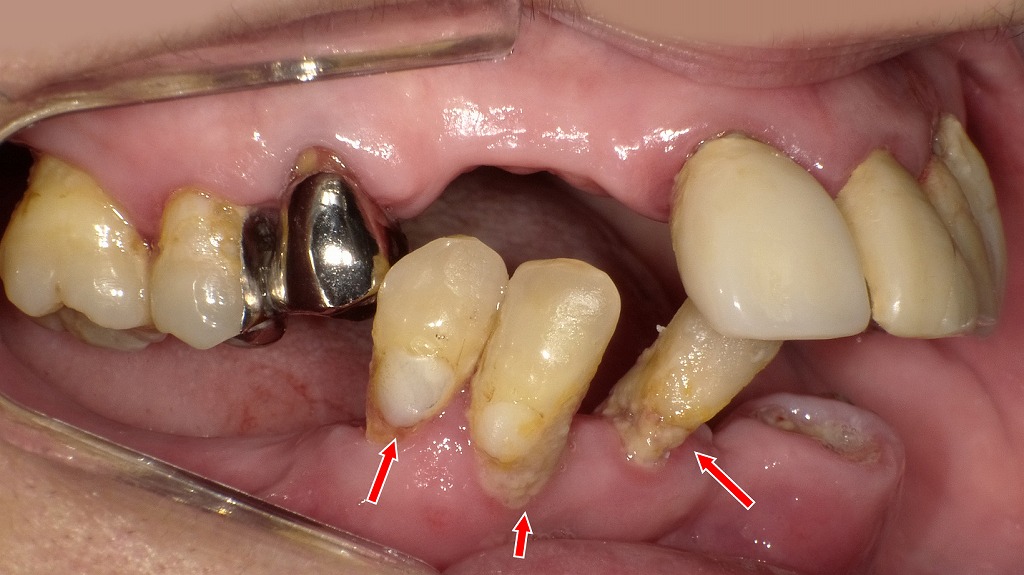

歯面にはプラーク・歯石の付着がみられ、歯ぐきは軽度に発赤し腫れを伴っています。これは歯周病の初期段階(P1〜P2)でみられる典型的な所見で、炎症が広がるとポケットの深さが増し、骨吸収が進行するとP3〜P4へ移行します。見た目の出血や腫れだけでは進行度を判断できないため、プロービングによる歯周検査と定期的なメインテナンスが重要です。

2枚目は、歯周病が最も進行した段階であるP4(重度歯周病)の症例です。歯肉の大きな退縮により歯根が露出し、歯槽骨は大幅に吸収されています。赤矢印部では歯の支持組織がほとんど失われ、歯の動揺や咀嚼障害が強く現れる状態です。この段階では自然回復は望めず、抜歯を含めた外科的対応や補綴治療を検討する必要があります。